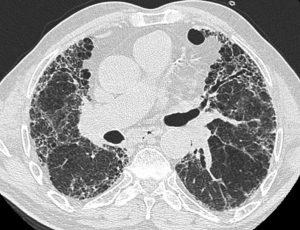

LPA1拮抗剂BMS-986278可降低进展性肺纤维化患者肺功能下降率

对于肺纤维化患者来说,良好的治疗选择一直以来都是急需解决的问题。然而,好消息是,布里斯托-迈尔斯-斯奎布(Bristol Myers Squibb)公司最近宣布了一项突破性研究,该研究关注一种潜在的新药BMS-986278,这是一种口服的溶磷脂酸受体1(LPA1)拮抗剂,用于治疗渐进性肺纤维化(PPF)患者。这项研究的结果表明,在为期26周的治疗中,每天两次口服60毫克的BMS-986278相对于安慰剂,减缓了预测强制性肺活量下降的速度,减幅达69%。这一突破性发现有望为肺纤维化患者带来新的治疗选择,提高其生存质量。 研究结果 这项研究是一项全球性的随机试验,研究对象分为两组,一组为原发性肺纤... 查看详情